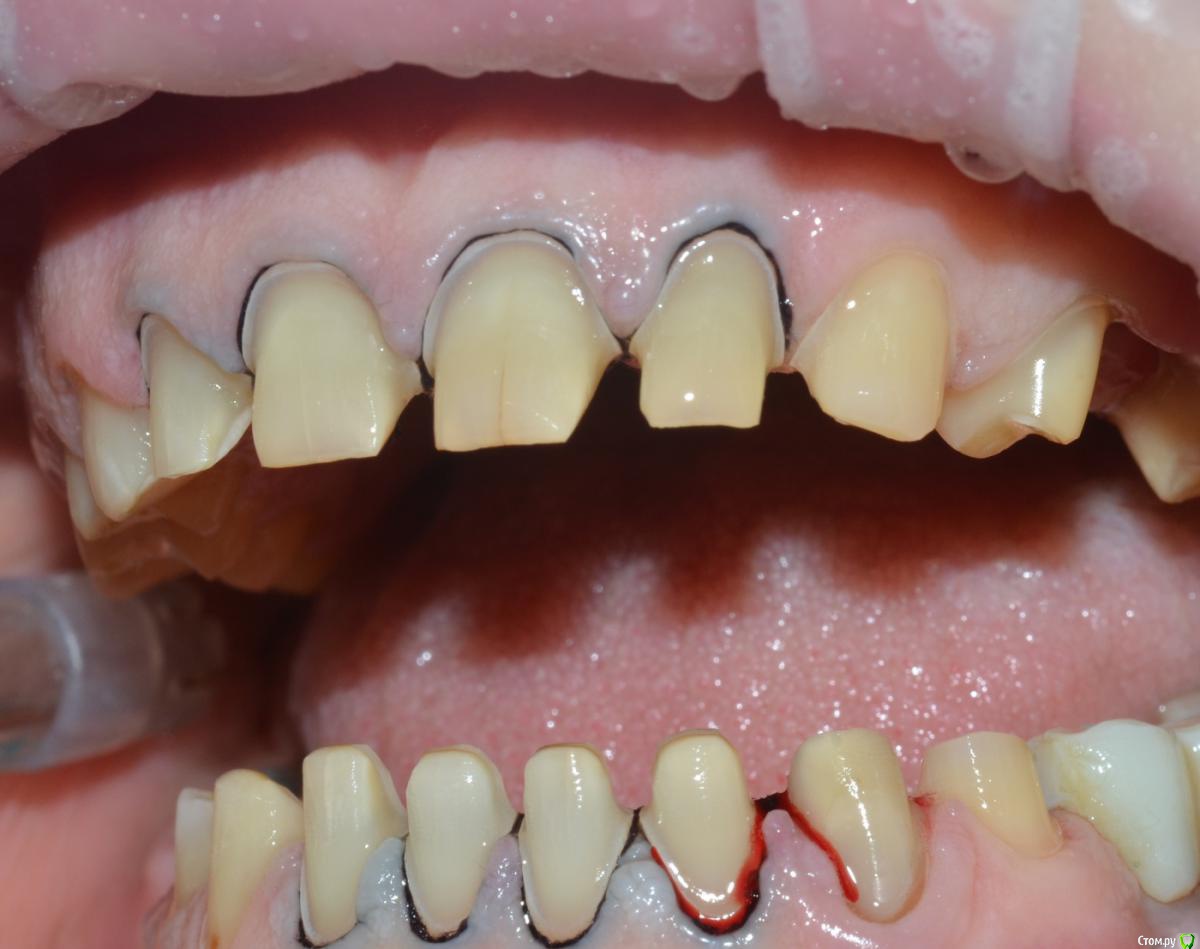

NazranDantist Опубликовано 4 сентября, 2015 Автор Поделиться Опубликовано 4 сентября, 2015 Продолжение кейса. Работа еще не закончена, зуб 25, 35, 36 - аббатменты на подходе, поэтому решили сделать после отпуска пациентки. Фото протокол не соблюдал, курс рубля прыгал, торопился в обменник . Вся работа - имакс на Цереке с редуцированием, фиксация - фронт на чойс, боковые - У-200. Ссылка на комментарий

CHEREDNICHENCO Опубликовано 12 сентября, 2015 Поделиться Опубликовано 12 сентября, 2015 Режет глаз смещение цл, оптг необходимо определенно, хотя бы для оценки состояния тттз и периапикальных тканей в 4 секторе.... Индикатор кариеса используете в работе???.... А зачем в 3 секторе оставили временную конструкцию?! Или это постоянная???..... В десятых- эстетически не вяжется соотношение нижних к верхним... PS: В связи с определенным географическим положением, КНДР находиться в 1 км. 44 м. от места моей работы! и хочу сообщить Вам,- уровень их работ растет от из года, в год! Ссылка на комментарий

CHEREDNICHENCO Опубликовано 12 сентября, 2015 Поделиться Опубликовано 12 сентября, 2015 До протезирования, без смещения! 1.5, 1.6 кариес II класс, 4.3 - V. Как сагиттальную окклюзионную кривую выводили??? Не проще было подождать подхода аббатов...со времянками? Ссылка на комментарий

NazranDantist Опубликовано 12 сентября, 2015 Автор Поделиться Опубликовано 12 сентября, 2015 (изменено) До протезирования, без смещения! 1.5, 1.6 кариес II класс, 4.3 - V. Как сагиттальную окклюзионную кривую выводили??? Не проще было подождать подхода аббатов...со времянками?Кариеса нет.Смещение есть Изменено 12 сентября, 2015 пользователем NazranDantist Ссылка на комментарий

CHEREDNICHENCO Опубликовано 13 сентября, 2015 Поделиться Опубликовано 13 сентября, 2015 Кариеса нет.DSC_0643.JPGСмещение естьПо фото, когда зубные ряды находятся в контакте- смещение есть! Но на первых фото, когда НЧ находиться в состоянии относительного физиологического покоя, смещения нет! ТО делаю вывод, смещение возникает в результате неправильного соотношения жевательных поверхностей зубов. Ссылка на комментарий